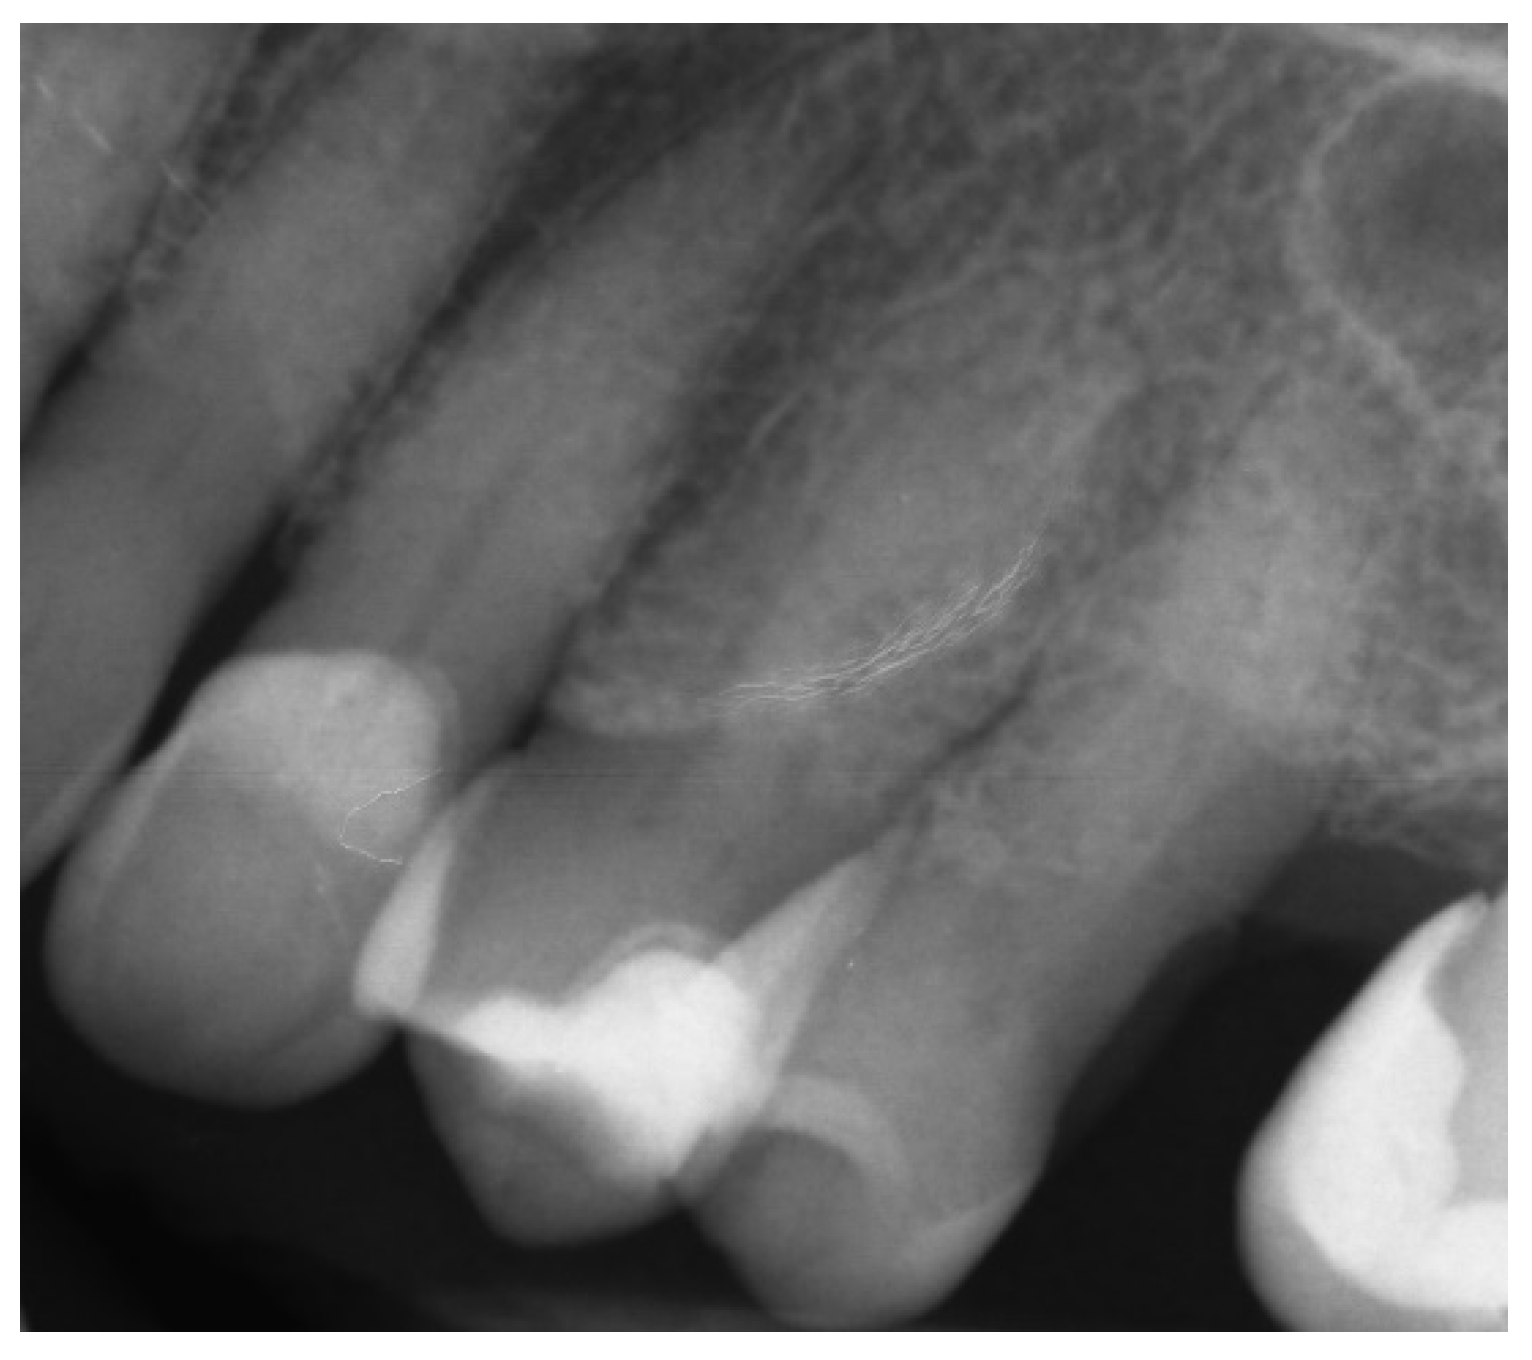

2.1.1. Case Report—Patient A: Symptomatic Pulp Necrosis after Trauma

2.1.2. Case Report—Patient B: Asymptomatic Pulp Canal Obliteration after Trauma in Tooth Requiring Prosthetic Treatment (Aesthetic Dental Crown)